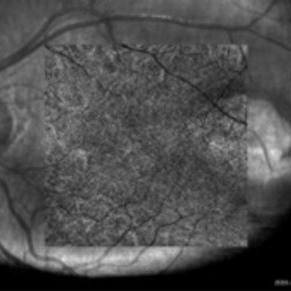

Superficial capillary plexus OCT-angiography of an asymptomatic 12-year-old girl with Torpedo maculopathy of the left eye. No abnormality.

Photographer: Pierre-Henry Gabrielle, Ophthalmology department, Dijon University Hospital, France

Imaging device: Zeiss Cirrus OCT

Condition/keywords: optical coherence tomography (OCT), torpedo maculopathy